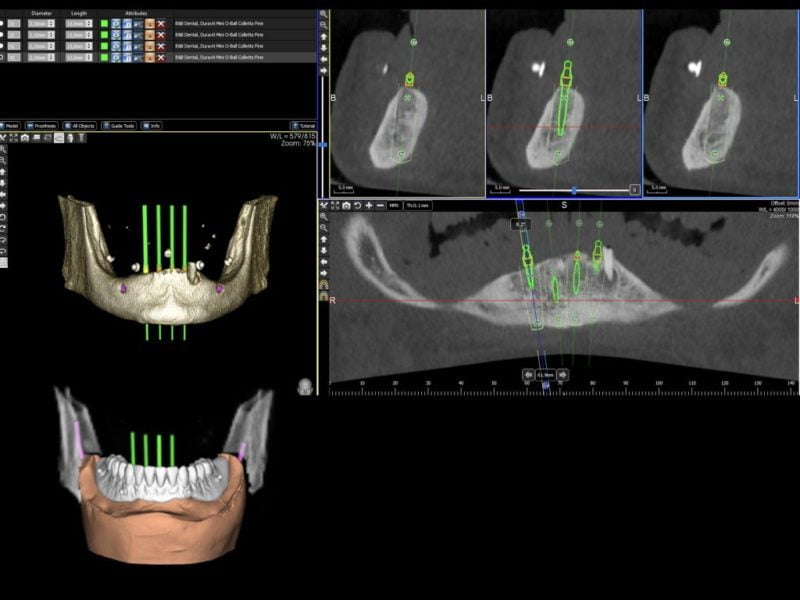

A 90-year-old female patient presented with an edentulous mandible (the lower left canine root was still present) in need of denture stabilisation. A Cone Beam CT scan was undertaken to establish bone volume and gain an accurate 3D image of the mandibular architecture. 3 Diemme (Cantù, Italy) planning software was utilised to plan the case and allowed for virtual implant placement to produce optimal positioning of the implants. In line with MDI protocol, these implants were planned to be placed inter-foraminally.

In this case, it was determined that four MDIs (MDI Implantology, Bologna, Italy) with a diameter of 2.1mm and a length of 13mm would be the most suitable implants to retain and stabilise the existing denture. Figures 1 and 2 show the virtual implant placement and a digital model superimposed on the tomograph showing the denture in place.

A drilling template was designed and verified via the software and produced by dental laboratory incorporating four guide sleeves with a diameter of 2.65mm to guide the drills in creating the osteotomies. Two further lateral guide sleeve were incorporated into the labial aspect of the guide to enable lateral fixation of the guide should it be required during surgery (figure 3).

The use of Cone Beam Computerised Tomography (CBCT) allows for virtual implant placement in planning software which allows a surgical guide to be produced allowing proper placement, spacing and parallel alignment of the implants. The guide also allows for a flapless procedure to be undertaken where there is sufficient bone width. This reduces patient morbidity and healing time as well as the benefit of reduced surgical time.